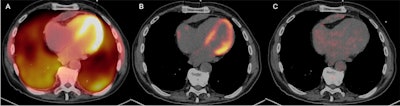

Having patients with cardiac sarcoidosis follow a ketogenic diet for three days before their PET/CT scans can improve image quality by suppressing signal from normal myocardial activity, according to a March 26 study in the Journal of Nuclear Medicine.

Researchers from the University of Minnesota compared more than five years of data on the effects of three different dietary modifications prior to FDG-PET/CT scans in patients suspected of cardiac sarcoidosis. They found that a 72-hour daytime ketogenic diet resulted in increased myocardium suppression and diagnosis rates.

Cardiac sarcoidosis is a rare disease characterized by the formulation of granulomas in the tissue of the heart, and it can cause arrhythmias and heart failure. FDG-PET/CT has emerged as a promising alternative to invasive biopsies for diagnosing the condition, yet for physicians to be able to differentiate between normal physiologic myocardial activity and abnormal myocardial inflammation, the patient's consumption of glucose needs to be suppressed.

- Diet A, a 24-hour ketogenic diet with overnight fasting (n = 94)

- Diet C, a 72-hour ketogenic diet with overnight fasting (n = 98)